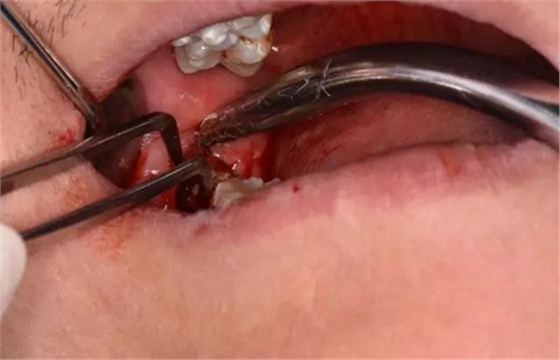

圖10.普通牙挺放置在48牙冠的近中面與牙槽嵴之間,先推后挺。

圖11.分別在近中和頰側(cè)反復(fù)用挺